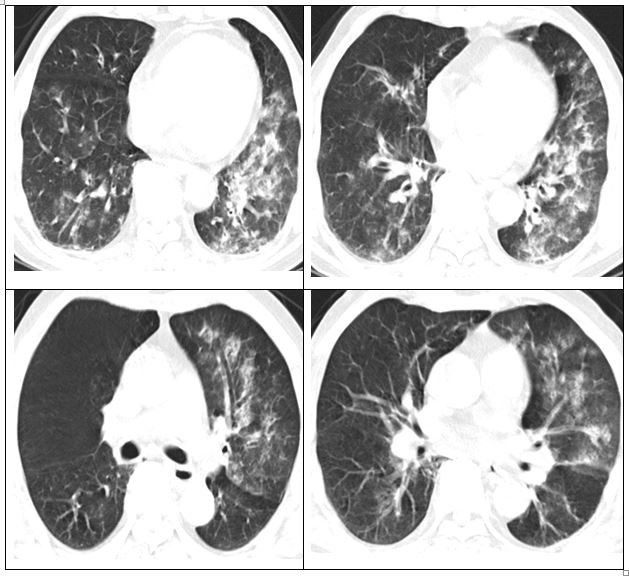

Người bệnh đã được khám và làm cận lâm sàng: test cúm A dương tính, CT ngực viêm phổi lan tỏa và đông đặc.

| Phổi đông đặc, suy hô hấp phải nhập viện |